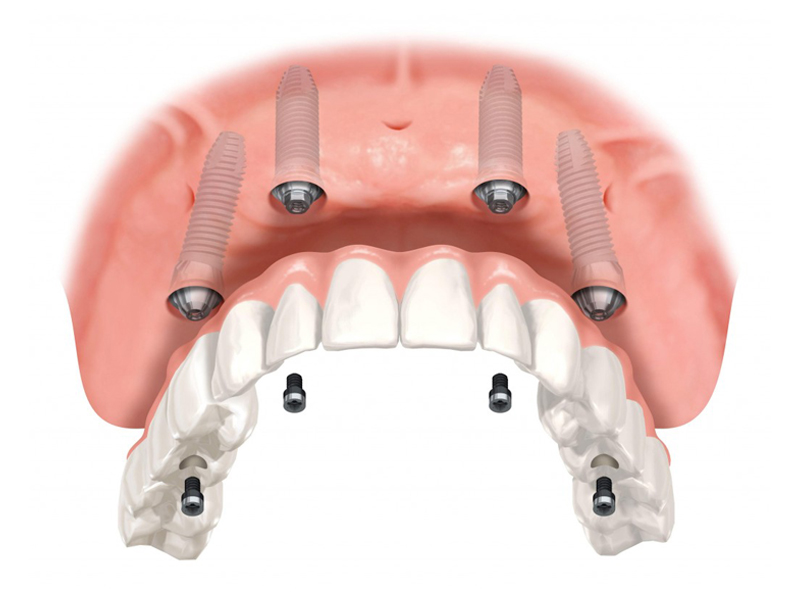

This method is aimed both at edentulous patients who want a fixed prosthetic restoration, and at patients who have an insufficient amount of bone necessary to insert implants and are not candidates for conventional implant-prosthetic therapy.

Using the All-On – 4 method; Dental implants are inserted in the same day and in a few hours, a temporary but fixed prosthetic job is performed immediately which will remain until the implants are perfectly integrated into the bone. After about 4-6 months, definitive prosthetic rehabilitation will be performed, which will be screwed onto existing implants. The screw fixing will allow you to remove the restoration (fixed bridge) when necessary.

The specificity of this procedure is that the teeth are fixed on four implants. Thanks to the particular method of inserting the implants, bone reconstruction is not necessary, which is instead a requirement when it is necessary to reconstruct in patients who have total tooth loss.

| absence of bone reconstruction |

| absence of the maxillary sinus lift and complex surgical procedures and represents a satisfactory aesthetic solution and allows correct oral hygiene maintenance. |